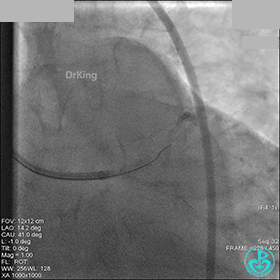

AL 1.0指引导管到位,简单短时尝试导丝不能顺利通过前降支或回旋支病变。改变策略处理右冠脉病变,计划植入2枚支架。AL指引导管到位,Sion blue导丝到达右冠脉远端。导丝通过后1.5mm及2.5mm球囊14~16atm充分扩张中段病变。

右冠脉中段充分扩张后欲植入3.5×38mm支架时,支架难以通过中远段扭曲处,且指引导管、导丝弹出飞扬。反复尝试导丝重新到达右冠脉远端时通过不顺利,局部造影剂滞留,远端血流接近3级。